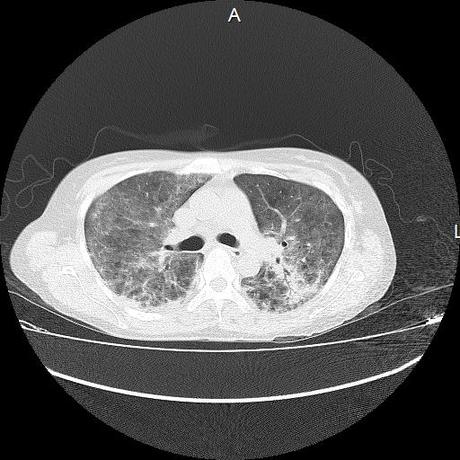

El parénquima pulmonar con areas parcheadas difusas en vidrio despulido combinadas con otras areas hipodensas de baja atenuación debidas a atrapamiento aéreo y engrosamiento intersticial y zonas de fibrosis de predominio en lóbulos medios e inferiores de ambos pulmones.

- LOS HALLAZGOS PUEDEN ESTAR EN RELACIÓN A NEUMOPATIA INTERSTICIAL PROBABLE ETIOLOGIA HIPERSENSITIVA VS AUTOINMUNE/BACTERIANA/FUNGICA.